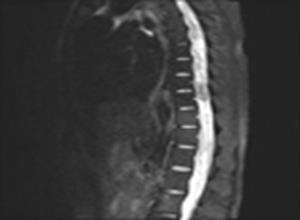

简介椎管内结核瘤系椎管内硬脊膜内或硬脊膜外侵犯脊髓的结核性肉芽肿。